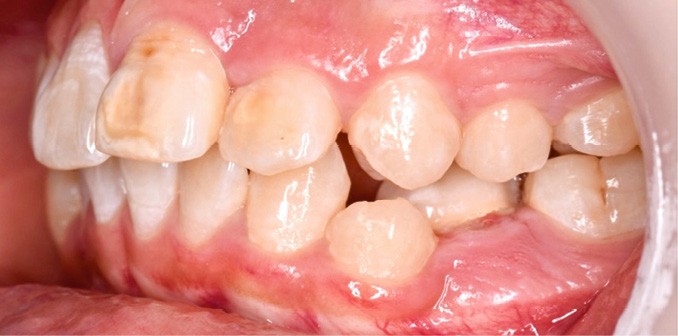

Une patiente âgée de 12 ans se présente en consultation, motivée par la position de son incisive centrale maxillaire, décrite comme « en avant », marquée par une dyschromie et une mobilité de grade 2 selon Muhlemann. L’examen clinique montre l’absence de 23 sur l’arcade, une dysharmonie dents-arcade marquée, un surplomb accentué, et une déviation des milieux inter-incisifs, conséquence du comblement spontané de l’espace de 23. L’ensemble s’inscrit dans un contexte de Classe I d’Angle molaire. L’orthopantomogramme révèle l’inclusion de 23, associée à une résorption radiculaire étendue aux deux tiers de 21. La 22 ne présente aucune altération visible.

La patiente, de profil normodivergent, présente une Classe I squelettique sans troubles fonctionnels (fig. 1-8).